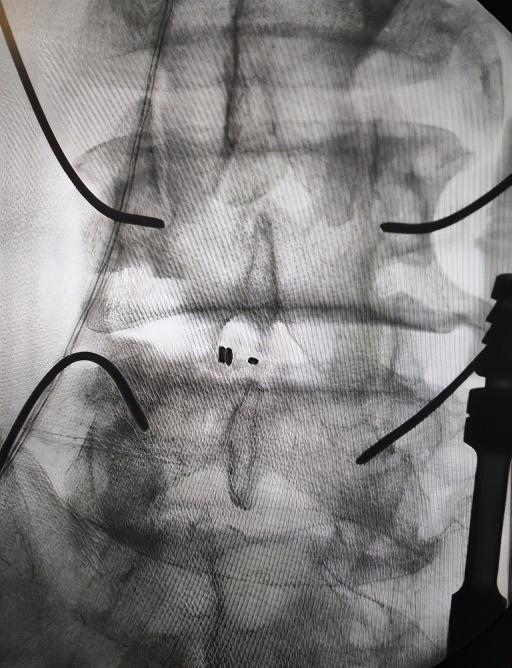

上图:在骨科机器人的精确定位下置入导针

脊柱科张冶副主任医师为老人作了仔细检查,患者L3/4、L4/5、L5/S1椎间盘突出,同时还有L4左侧腰椎椎弓峡部裂。尚军主任和张冶医生反复讨论病情,研究影像资料,决定采用天玑骨科机器人辅助,为老人进行“腰椎后路减压+内固定+融合术”手术。跟传统手术相比,骨科机器人辅助,是一种安全高效的手术方案。“一是手术切口小,二是精准定位置钉,患者早期下地、伤口更小、出血量更少、疼痛感更轻、术后恢复更快,具有很多优势。”